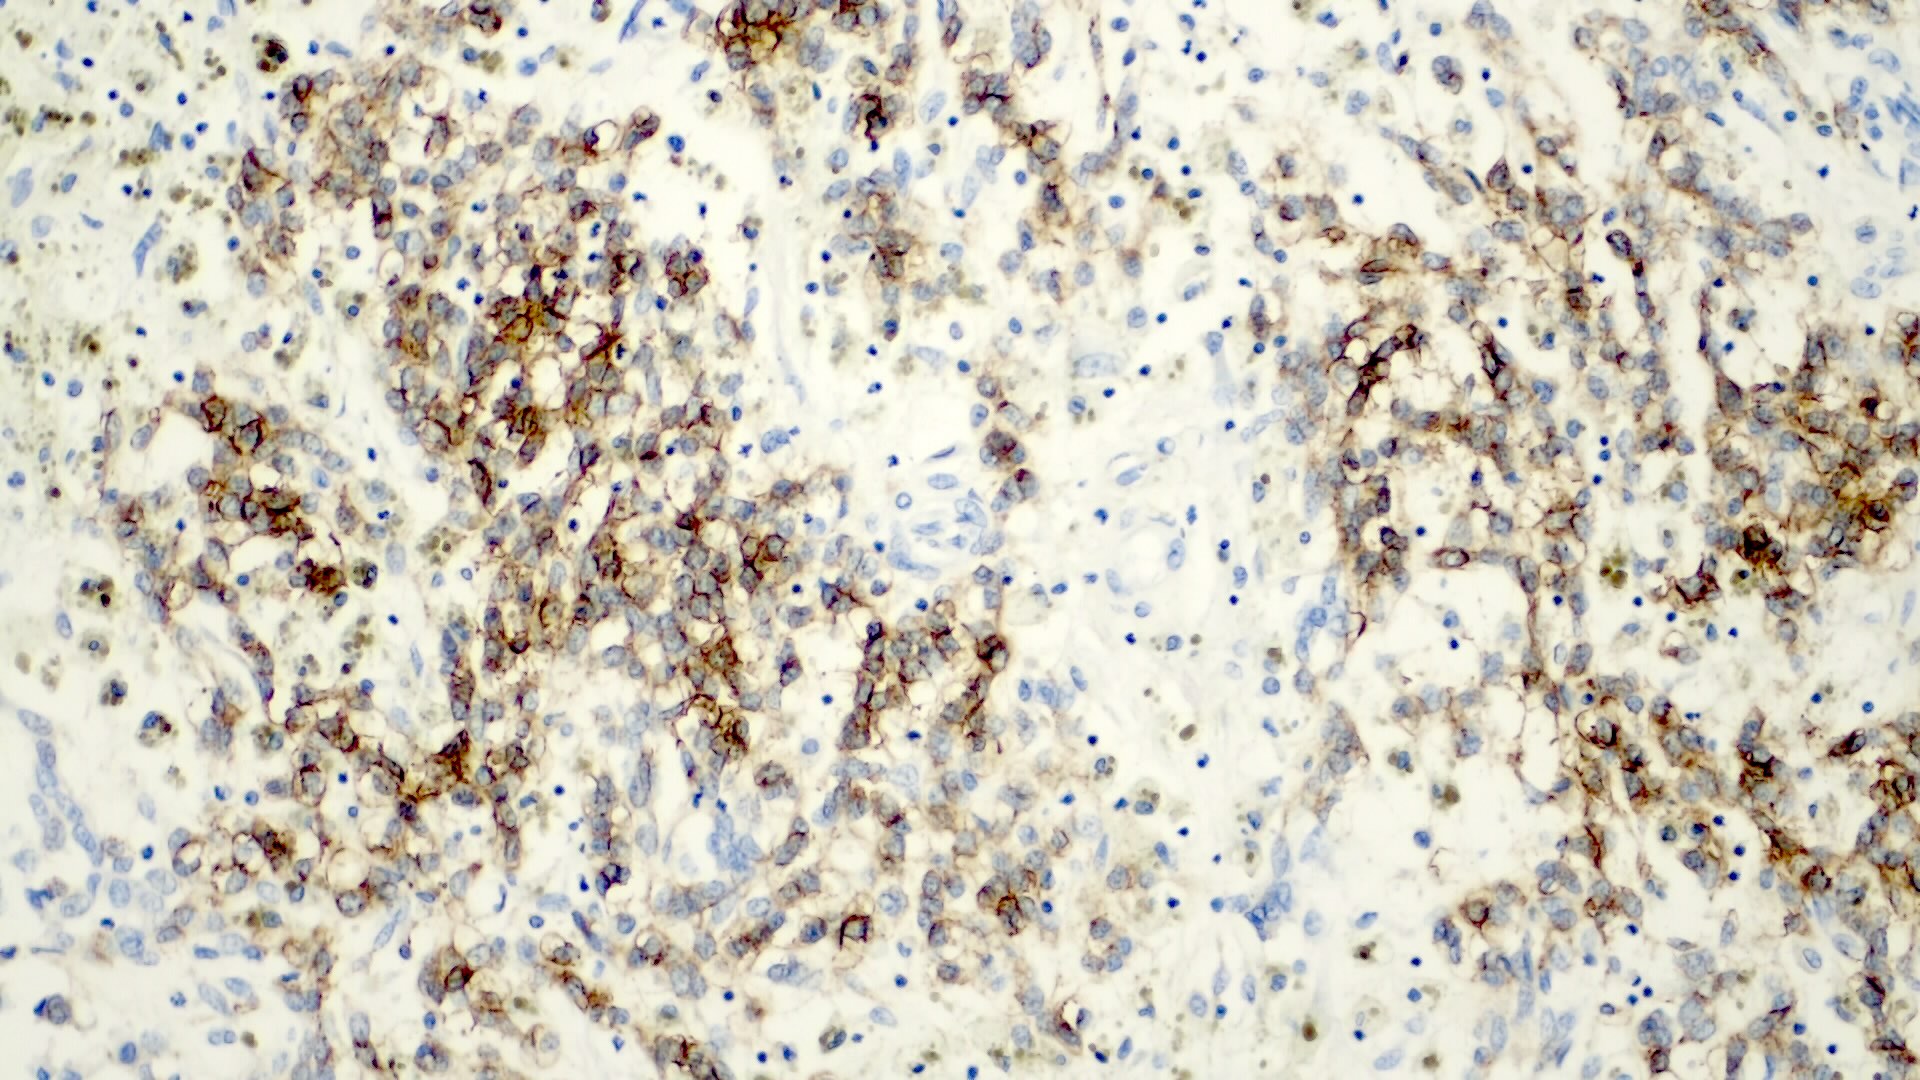

Positive stains

- Alpha fetoprotein (negative in small cell type), chromogranin (fetal, epithelial subtypes, usually focal), CK8 / 18 (fetal, epithelial subtypes), CK19 (embryonal subtypes)

- Also EMA, HepPar1 (negative in small cell type), polyclonal CEA (canalicular pattern), vimentin

- Variable hCG, occasional HMB45 and melanin

- Beta catenin (nuclear) in small cell and embryonal types, delta-like protein (DLK), glypican 3 (negative in small cell type), glutamine synthetase

Positive stains

- Frequent beta catenin and glutamine synthetase in the epithelial fetal (except the well differentiated and low mitotic subtype) and mesenchymal patterns (Pediatr Dev Pathol 2020;23:79, Biosci Rep 2019;39:BSR20192466)

- AFP in the less differentiated epithelial components

- HepPar1 in the fetal pattern

- Polyclonal CEA

- Glypican 3 in the fetal and embryonal pattern

- Pancytokeratins have variable expression (J Gastrointest Oncol 2018;9:326)

- CK7 and CK19 in the cholangioblastic pattern (J Gastrointest Oncol 2018;9:326)

- INI1 / SMARCB1 usually retained